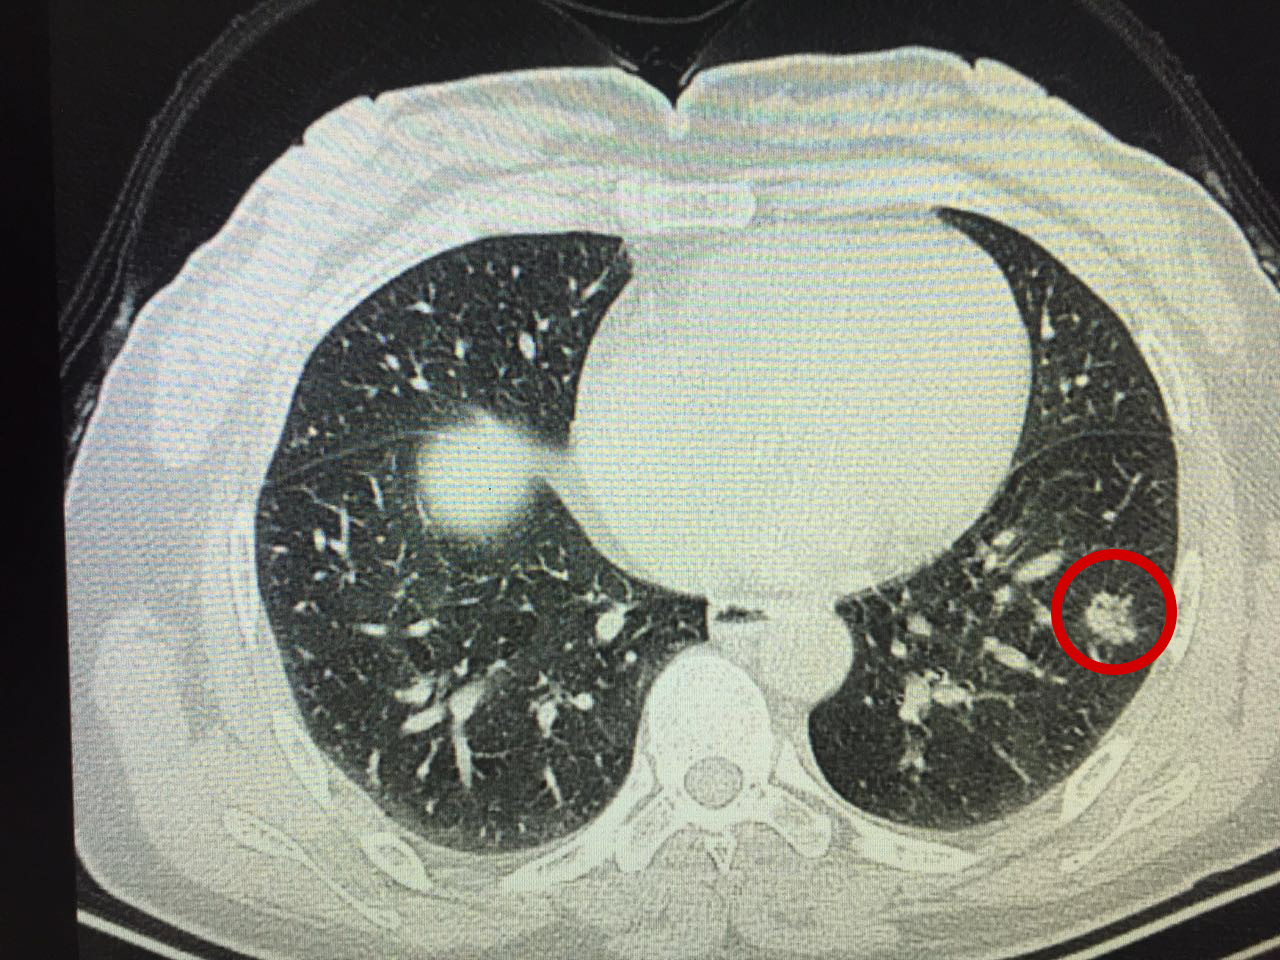

“医生,我感觉胸闷不舒服,还有点咳嗽,有点像感冒但感觉又不是。”海宁的吴女士(化名)走进海宁康华医院的内科诊室,向医生描述了自己的病症。初步查看过吴女士的症状后,医生建议她拍一个胸部CT。而CT结果一出来,吴女士傻眼了——肺部有35px小结节,不排除肺癌可能!

吴女士赶紧找到康华医院肺结节中心的主任、副主任医师王剑飞确诊。反复研究胸片后,王剑飞建议吴女士先入院治疗,通过消炎、雾化吸入、中药等进行调理干预,进一步确认该结节的良恶性。

“情况还不错。”王剑飞原本严肃的脸上此刻挂上了淡淡的微笑,“你看,虽然大小几乎没变,但是变淡了,这是好现象。”他指点着结节部位,又调出之前的片子做对比。